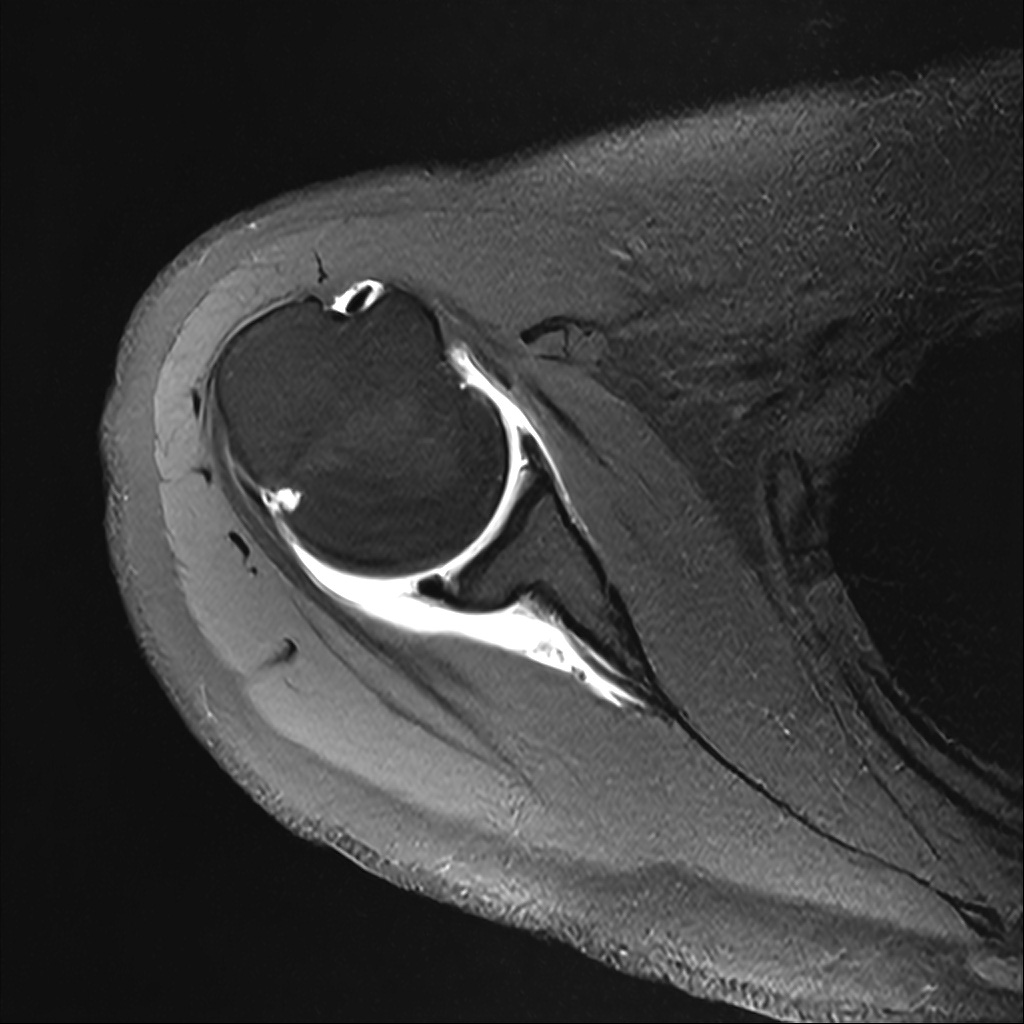

Mri 단면 영상으로 보아 어깨 관절 부위에서 이상 신호가 관찰되고 이는 관절 와순 파열의 가능성을 시사할 수 있습니다.

하지만 이영상만으로 정확한 진단은 불가능하고 정밀한 판단을 위해선 전체 시퀀스와 영상의학과 전문의의 공식판독이 필요합니다 특히 와순 파열은 위치와 동반 병변에 따라 해석이 달라집니다!